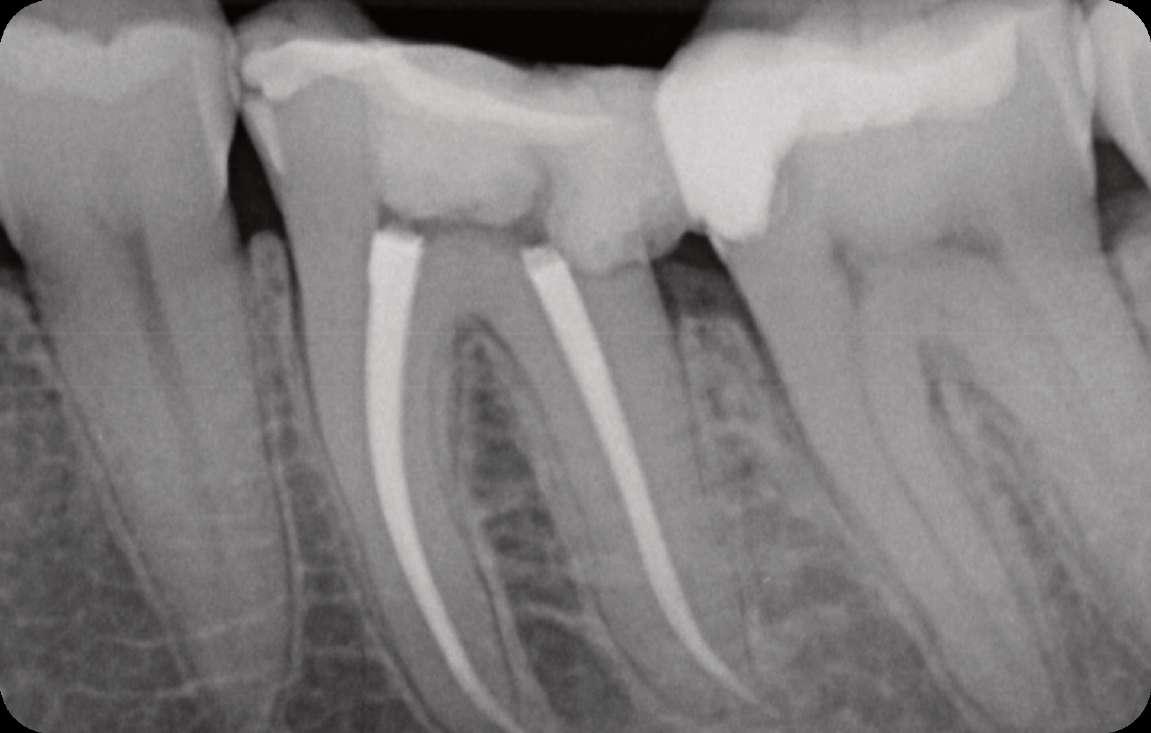

Das Röntgenbild zeigte eine große Länge und einen gemeinsamen Ausgang für zwei der drei mesialen Kanäle.

Die Wurzelfüllung erfolgte mit einer einzigen Kegeltechnik unter Verwendung des BUSA EndoSequence Bioceramic Sealer. Das Post-OP-Röntgen zeigt sehr hohe Dichte in der gesamten Länge der Wurzelfüllung.